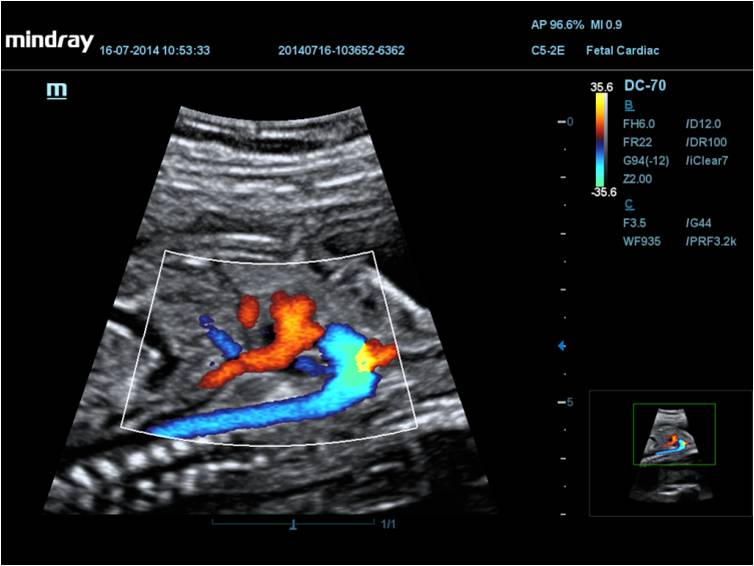

Mindray DC-70 Exp с технологией X-Insight – это узи-аппарат для высококачественной диагностики. Преимущества: высокая эффективность, точность визуализации, результат в «одно касание» с экспертными датчиками. Рекомендуется для государственных учреждений.

• Кардиология